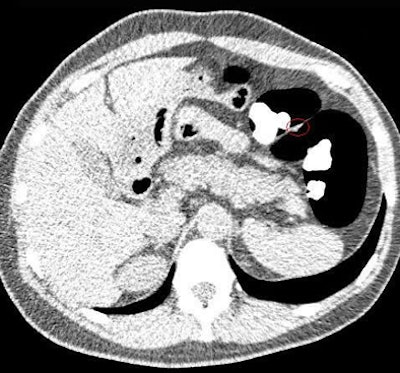

All CTC exams in the study were performed on a 64-slice CT scanner (Aquilion 64, Toshiba Medical Systems, Tokyo) in a cohort of subjects who underwent one of two types of bowel preparation before scanning, followed by optical colonoscopy.

Colonic insufflation was performed using manual room air, Yoshida said, noting that automated CO² insufflation is not yet approved for use in Japan. Overall, distension proved to be adequate, he said.

The biggest challenge was the residual fluid seen in some PEG-prepped cases owing to a lack of electronic cleansing software, especially when untagged feces were present, Yoshida said. For this reason, all studies were read using a primary 2D approach, with 3D confirmation of findings performed "whenever possible," he said.

The CT datasets were postprocessed using commercially available software (Ziostation system 510, Ziosoft, Redwood City, CA).